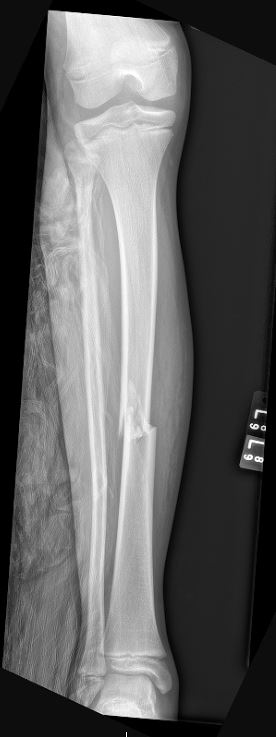

Tibia Shaft Fracture